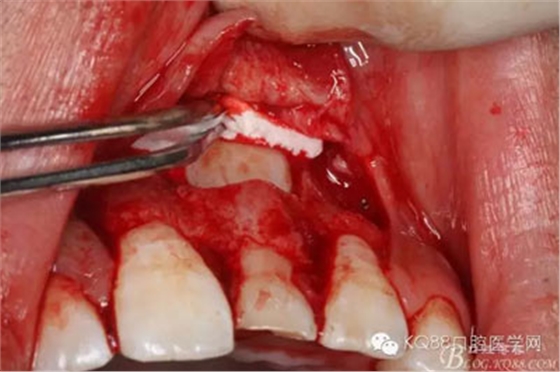

圖15.輕輕的把21牙冠牽引至乳Ⅰ根尖方向,并擺正牙冠位置。(拔苗助長)

圖16.牙冠上方覆蓋膠原蛋白膜

圖17.骨壁重新覆蓋回去

圖18.縫合